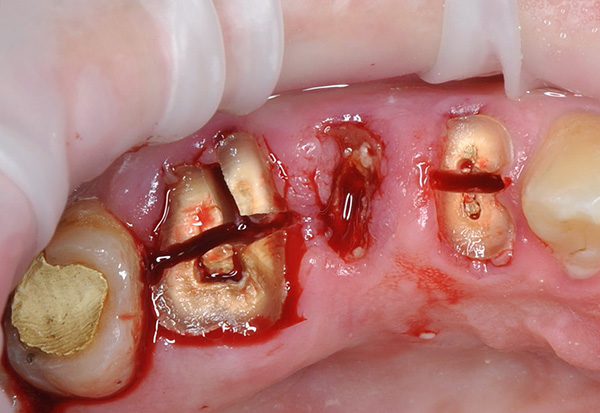

A imagem abaixo mostra um dente do siso retardado: